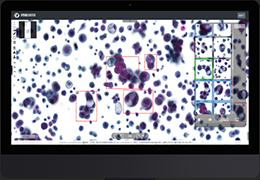

ART-Plan™ Artificial Intelligence Contouring